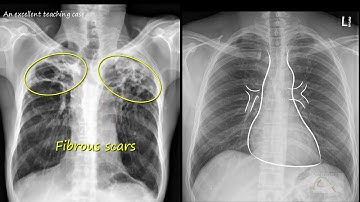

Automatic Tuberculosis Detection Using Chest X ray Analysis With Position Enhanced Structural